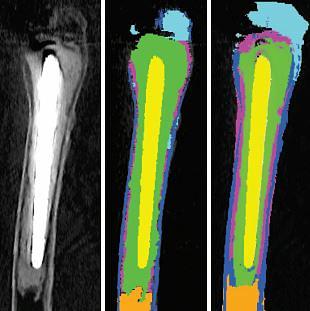

We present an automated algorithm which classifies periprosthetic tissues in CT scans of patients with loosened hip prostheses. To our knowledge this is the first application of CT voxel classification to periprosthetic tissues of the hip. We use several image features including multi-scale image intensity, multi-scale image gradient and distance metrics. Seven classifier types were trained using five manually segmented clinical CT datasets, and their classification performance compared to manual segmentations using a leave-one-out scheme. Using this technique we are able to correctly segment the majority of each of the six tissue categories, in spite of low bone densities, metal-induced CT imaging artefacts and inter-patient and inter-scan variation. Our automated classifier forms a pragmatic first step towards eventual automatic tissue segmentation.